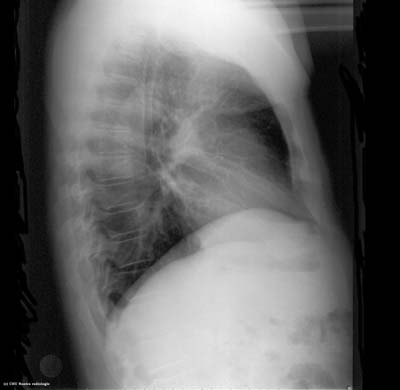

Cliché thoracique de profil